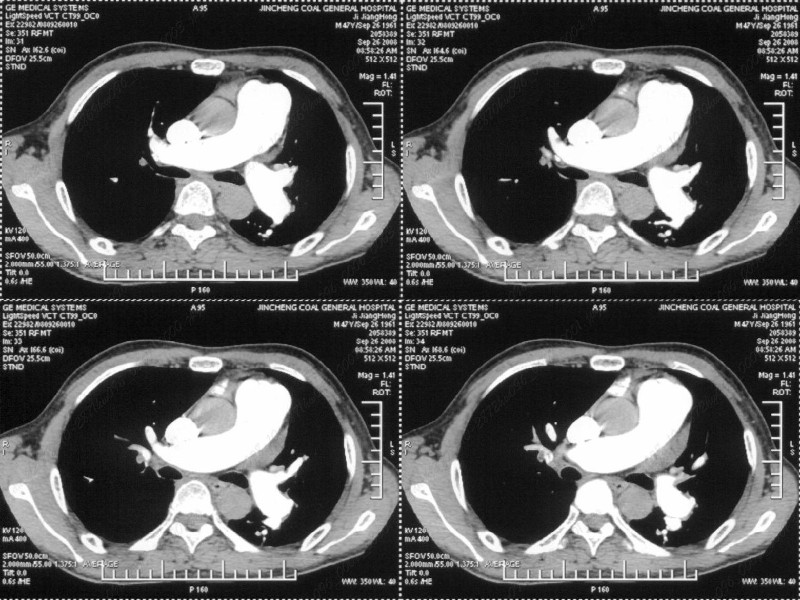

男性,47岁。胸部不适一年,ct检查发现右胸膜下结节。http://www.radida.com/bbs/forum.php?mod=viewthread&tid=46094

右前胸膜下小结节,边缘有小纤维条索影与胸膜粘连,考虑如炎性假瘤之类慢性病变可能。期待二周后的结果。

汇报临床诊断:右肺动脉分枝栓塞

肺内小结节与肺动脉分支栓塞不一定有直接关系.

右肺静脉充盈缺损,左心房体积小,右肺动脉远端动脉充盈缺损,右肺血管影细小,考虑;右肺动脉远端栓塞.